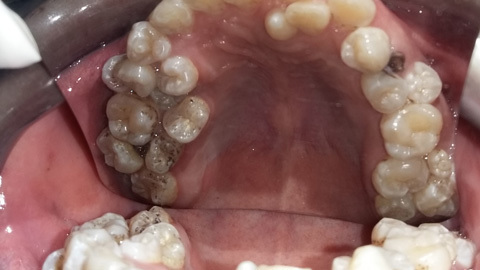

Hy hữu: Răng mọc tua tủa trong miệng chàng trai 28

Đến bệnh viện để xử lý răng sâu nhưng các bác sĩ đã vô cùng ngỡ ngàng khi phát hiện bệnh nhân thừa đến gần 20 cái răng.